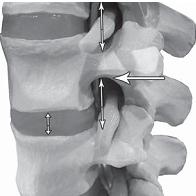

Тракционные методы лечения— вытяжение Слово тракция образовано от латинского слова tracto, что означает «тянуть», «тащить». Проще говоря, это вытяжение (лат. extensio). Вытяжение считается одним из основных ортопедических методов лечения, который применяется при повреждении и заболевании опорно-двигательного аппарата и их последствий. Суть данного метода заключается в том, что с помощью длительной или кратковременной тяги, применяемой в качестве противодействия естественному напряжению тканей, окружающих повреждённое место (к примеру сломанную кость), устраняется смещение отломков при переломе или же оказывается растягивающее действие на ту или иную область человеческого тела с целью устранения деформации или контрактуры (ограничения подвижности). Лечение переломов костей, вывихов суставов с помощью определённых конструкций и аппаратов вытяжения было известно издревле. В своей медицинской практике их использовали такие исторические личности, как знаменитый врач, писатель Древнего Рима Клавдий Гален (II в. н. э.), великий среднеазиатский философ и врач Ибн-Сина (Авицена, XI век), один из выдающихся хирургов Средневековья французский врач Ги де Шолиак (XIV век). Фактически внедрение данного метода в активную практику началось лишь с XIX века, когда известный немецкий хирург, профессор Бернгард Барденгейер опубликовал капитальный труд о повреждениях конечностей, в котором предложил метод лечения переломов посредством вытяжения, сформулировав его основные положения. В травматологии при свежих вывихах, переломах костей метод вытяжения действительно весьма эффективен. Одним из недостатков метода вытяжения при переломе кости считается длительная вынужденная иммобилизация пациента, которая негативно сказывается на его общем состоянии. Тем не менее, ради того чтобы кость срослась правильно, стоит потерпеть такие временные неудобства. Однако если в травматологии при переломах костей метод вытяжения вполне себя оправдывает, то при лечении дегенеративно-дистрофических процессов в позвоночнике (тем более осложнённых протрузиями или грыжами межпозвонковых дисков), как показывает практика, тракционные методы лечения оказываются не только неэффективными, но и усиливающими и ускоряющими процессы дегенерации. Обращаю ваше внимание на то, что применение метода вытяжения при лечении остеохондроза позвоночника — вопрос в научных кругах до сих пор спорный, имеющий много весьма существенных нареканий. Однако об этом, естественно, пациент не услышит ни в современной рекламе про разнообразные методы вытяжения позвоночника (тракционной терапии), ни в самих центрах, где практикуются данные методы. Наоборот, в рекламных буклетах можно прочитать следующее: — «вытяжение позвоночника является эффективным средством лечения смещения дисков, сопровождающегося их выпячиванием»; — «является одним из основных методов лечения неврологических проявлений остеохондроза позвоночника»; — «тракционная терапия позволяет производить безоперационное лечение грыж межпозвонкового диска»; — «вытяжение проводится, в первую очередь, для устранения болевого синдрома». Последнее, как правило, выделяется особым шрифтом, чтобы пациент не пропустил главной зацепки для своего сознания «в первую очередь для устранения болевого синдрома», то есть следствия заболевания позвоночника, и не очень задумывался о причинах возникновения своей болезни и тем более о дальнейших последствиях такого «эффективного лечения». Однако давайте подробнее разберёмся, что такое вытяжение позвоночника, за счёт каких механизмов идёт временное устранение болевого синдрома и к каким последствиям это приводит в дальнейшем. Как вы помните, позвоночно-двигательный сегмент является структурой трёхопорной (межпозвонковый диск и два дугоотростчатых сустава, на которые приходится вся нагрузка от веса вышележащей части тела и мышечных усилий). Чтобы понять суть данного метода, для начала рассмотрим на макете позвоночника, что происходит в процессе вытяжения с межпозвонковым сегментом. ![]() На фото № 4 макета позвоночника наблюдается нормальное взаимоотношение суставных поверхностей в дугоотростчатых суставах. На фото № 5 — нормальное взаимоотношение суставных поверхностей в дугоотростчатом суставе (увеличенный вариант).

На фото № 6 макета позвоночника наблюдается смещение (подвывих) суставных поверхностей дугоотростчатых суставов. На фото № 7 наблюдается смещение (подвывих) суставных поверхностей дугоотростчатого сустава (увеличенный вариант). ![]() На фото № 8 макета позвоночника наблюдается перерастяжение дугоотростчатых суставов вследствие вытяжения. На фото № 9 наблюдается перерастяжение дугоотростчатого сустава (увеличенный вариант). ![]() Фото № 10 На фото № 10 макета позвоночника наблюдается нормальное взаимоотношение суставных поверхностей дугоотростчатых суставов, в норме высота межпозвонкового диска и межпозвонковых отверстий. ![]() Фото № 11 На фото № 11 макета позвоночника наблюдается смещение (подвывих) суставных поверхностей дугоотростчатых суставов. Подобное смещение, как правило, происходит вследствие развития дегенеративно-дистрофических процессов в межпозвонковом диске. При этом уменьшается высота диска, сужается просвет фораминального отверстия (межпозвонкового), что может способствовать ущемлению спинномозговых корешков (нервов) и сосудов. ![]() Фото № 12 На фото № 12 макета позвоночника наблюдается перерастяжение дугоотростчатого сустава вследствие вытяжения, расширение фораминального отверстия, а также растяжение задних отделов фиброзного кольца межпозвонкового диска и сближение вентральных (передних) отделов тел позвонков. Это приводит межпозвонковый диск в клиновидное состояние, что способствует выталкиванию содержимого межпозвонкового диска из передних его отделов в задние. |